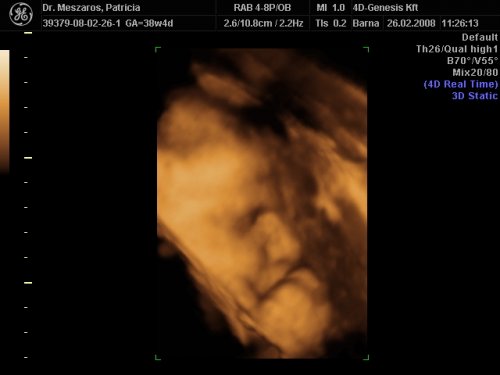

A doki szerint pufók kislány